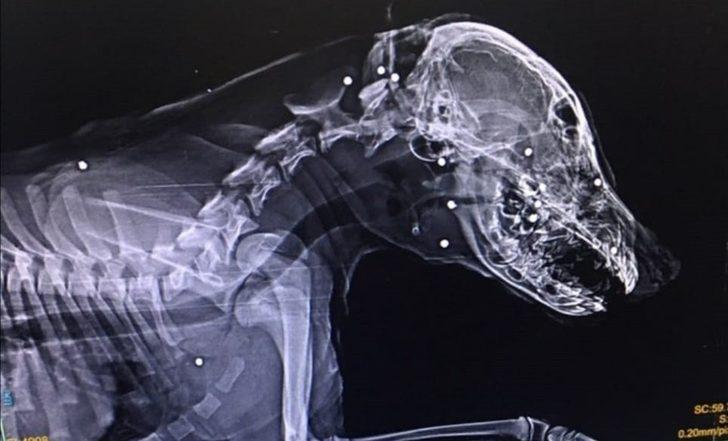

Zonguldak’ın Devrek ilçesinde sahipli bir köpek kimliği belirsiz kişilerce tüfekle suratından vurularak ağır yaralandı.Edinilen bilgiye göre, Zonguldak’ın Devrek ilçesinde Mert Ekşi’ye ait aylık sahipli köpek kimliği belirsiz kişi veya kişilerce tüfekle suratından vurularak ağır yaralandı.

Edinilen bilgiye göre, Zonguldak’ın Devrek ilçesinde Mert Ekşi’ye ait aylık sahipli köpek kimliği belirsiz kişi veya kişilerce tüfekle suratından vurularak ağır yaralandı. Devrek Mekekler Caddesinde meydan gelen olayla ilgili Devrek Emniyet Müdürlüğüne şikayette bulunan Mert Ekşi, ”Bunu yapanlar insan olamaz bu hayvanı ateş ederek yaralayanların bulunmasını ve adalet önüne çıkarılmasını istiyorum” diye konuştu.

Tedavisi için köpeğini aracıyla Zonguldak’a götüren Ekşi’nin köpeğini vuran veya vuranlar için polis geniş çağlı soruşturma başlattı